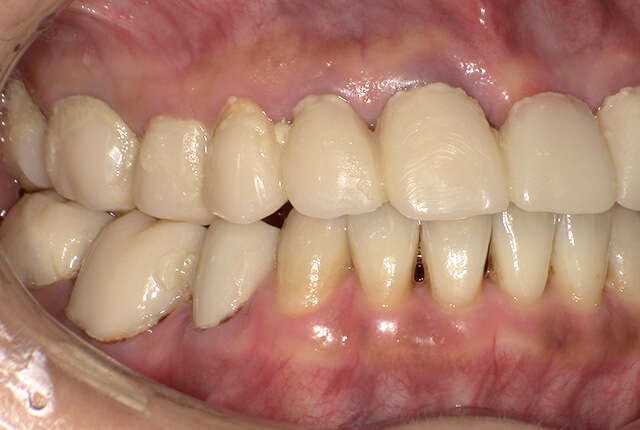

| 主訴 | ブリッジ脱離、しっかり噛めない |

| 診査診断 | 上顎歯牙欠損、歯周病、不良補綴、根尖性周囲炎。 不正咬合により噛み合わせのバランスが悪い事が原因により咬合治療が必要。 |

| 治療内容 | 欠損部インプラント 不正咬合に対し不良補綴のやり直しと合わせて咬合再構築 |

| 治療期間 | 4ヶ月 |

| 費用 | 200万円 |

| リスク | インプラントや被せ物の治療には、腫れや痛み、感染、破損、ゆるみなどが起こる可能性があります。 |